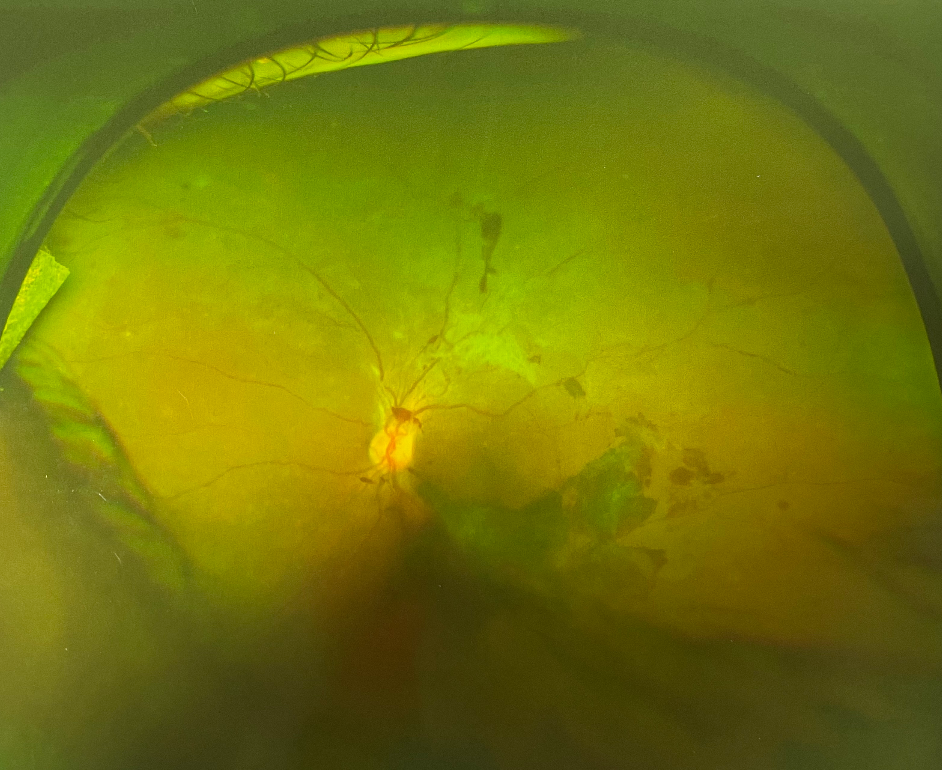

視網(wǎng)膜眼底出血,是眼底血管性病變的一種共同表現(xiàn)。

全身性血管、血液性病變都可以從視網(wǎng)膜及其血管反應(yīng)出來,同時也可直接引起視網(wǎng)膜出血性病變。

視網(wǎng)膜眼底出血

糖網(wǎng)早期僅表現(xiàn)為少量點狀出血,伴微血管瘤,隨病程進展可出現(xiàn)點片狀出血和滲出,一旦病變進展到增生期或出現(xiàn)黃斑水腫,視網(wǎng)膜新生血管會導(dǎo)致視網(wǎng)膜前大量出血或玻璃體出血,患者出現(xiàn)視力驟降,嚴重者幾乎什么都看不見。